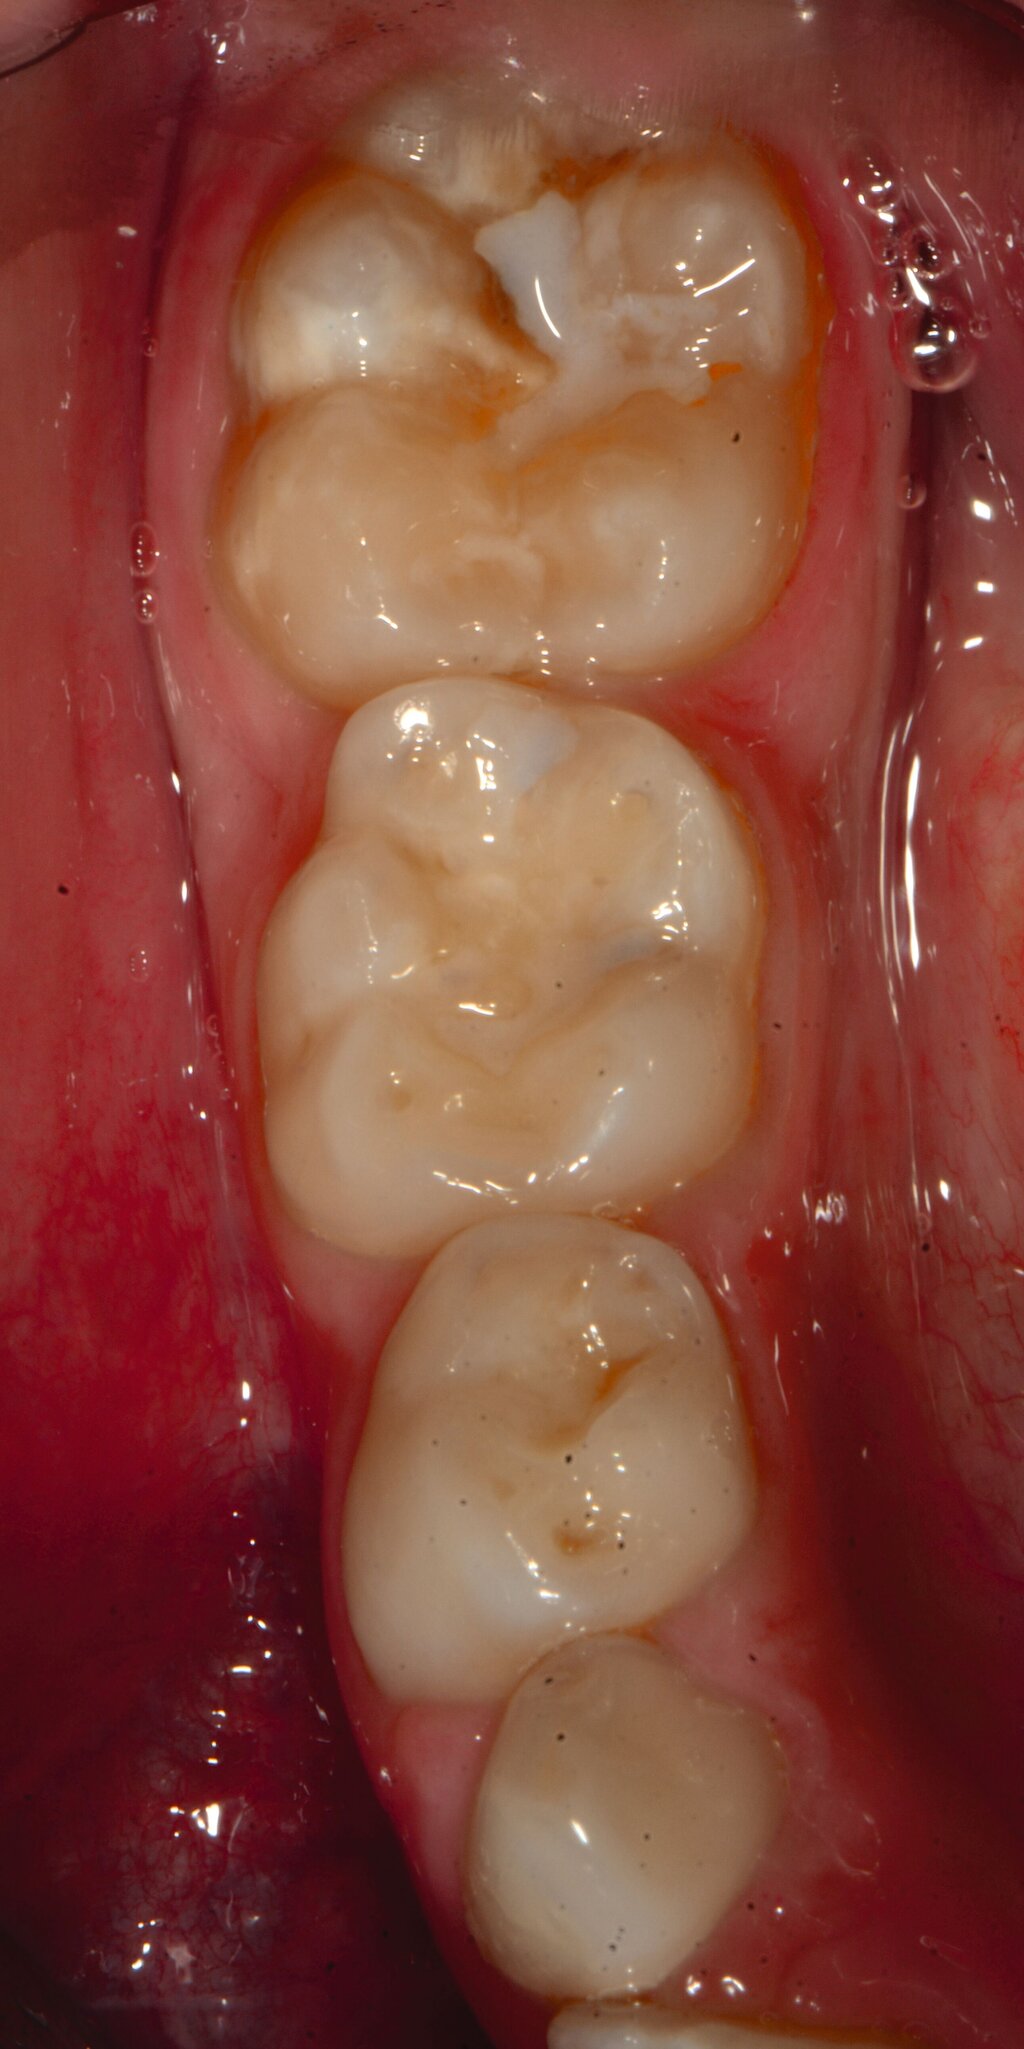

Die MIH (Abbildungen 1 und 2) stellt eine Strukturstörung der Zähne dar, die sich während der Zahnentwicklung manifestiert und daher bereits vor dem Durchbruch des Zahns in die Mundhöhle vorhanden ist. Obwohl der Name suggeriert, dass die ersten bleibenden Molaren und bleibenden Inzisiven die bevorzugten Indexzähne beziehungsweise Zahngruppen in der bleibenden Dentition sind, nutzt die Definition der European Academy of Paediatric Dentistry (EAPD) ausschließlich die ersten bleibenden Molaren zur Diagnosestellung. Entsprechend dieser Vorgabe muss zumindest ein erster bleibender Molar Zeichen einer MIH-bedingten Strukturstörung aufweisen [Lygidakis et al., 2010, 2022], damit die Diagnose einer MIH gestellt werden kann.

Das klinische Erscheinungsbild an bleibenden Zähnen zeigt typischerweise weißlich-gelbe bis gelblich-braune Opazitäten, die zumindest in einigen Bereichen durch eine scharfe Abgrenzung (engl.:„demarcated opacities“) zum gesunden Zahnschmelz charakterisiert sind (Abbildungen 3 und 4). Die abgegrenzten Hypomineralisationen befinden sich mehrheitlich im Bereich der inzisalen Kronenhälfte unabhängig von dem Auftreten an Front- oder Seitenzähnen. Die Ausprägung am Zahn kann dabei auf einzelne Areale oder Höcker begrenzt sein.

Bei einer schwerwiegenderen Ausprägung sind Zahnflächen vollständig betroffen, mitunter alle Zahnflächen an einem Zahn. Die Verteilung in der Dentition beziehungsweise an den Indexzähnen ist gleichermaßen variabel und betrifft nicht nur die Defektgröße, sondern auch die Farbe und Festigkeit. Was die Festigkeit betrifft, gilt als die Faustregel: Je dunkler die Farbe des Schmelzes, umso weicher beziehungsweise poröser und damit minderwertiger wird dessen Qualität sein. Damit reduziert sich seine kaufunktionelle Belastungsfähigkeit, was insbesondere an ersten bleibenden Molaren von klinischer Relevanz ist.